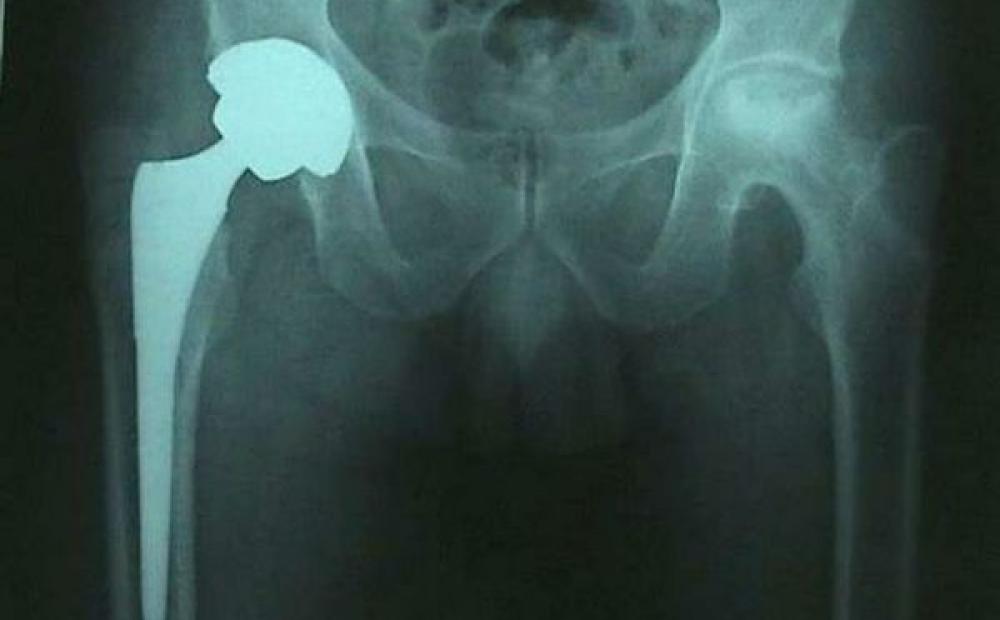

Preoccupazione in Veneto per le protesi d'anca difettose prodotte dalla multinazionale De Puy. L'Ulss n.3: “Al San Bassiano utilizzate protesi assolutamente sicure per durata e innocuità”

Le protesi d'anca in questione sono prodotte dalla De Puy, azienda del gruppo americano “Johnson & Johnson”, che ha comunicato ai propri clienti - Asl e ospedali privati in tutta Italia - un'anomalia riscontrata nei due modelli “XL Acetabular System” e “Hip Resurfacing System”: due tipi di protesi destinate soprattutto ai pazienti più giovani.

Secondo quanto riferito dalla multinazionale ortopedica, nelle due tipologie di protesi - basate sul sistema “metallo-metallo” - è stato constatato che dallo sfregamento delle due componenti metalliche si crea un'usura veloce e si liberano soprattutto delle sostanze nocive che possono causare infiammazioni.

“L’intervento di protesi d’anca con metodica francese, per cui l’ospedale di Bassano e l’equipe del primario ortopedico Enrico Sartorello sono ormai rinomati in tutto il Triveneto - afferma ancora il comunicato - viene eseguito utilizzando protesi assolutamente sicure sia nella durata che nell’innocuità”.

“Noi utilizziamo un tipo di protesi e delle procedure di intervento che danno ottimi risultati in termini di quantità di cure e qualità della vita - specifica la nota dell'Azienda sociosanitaria di Bassano -. La tecnica usata ha vantaggi per il paziente e per l’organizzazione delle attività ospedaliere (il paziente è autosufficiente, a casa sua, nel giro di una settimana), delle prestazioni di riabilitazione (il paziente abbandona le stampelle dopo 20/30 giorni dall’intervento, anziché dopo 60). Soprattutto garantisce alla persona la ripresa (a convalescenza avvenuta) di attività fisico sportive come il camminare, il nuoto, o la bicicletta senza alcuna limitazione nello sforzo e nella durata”.